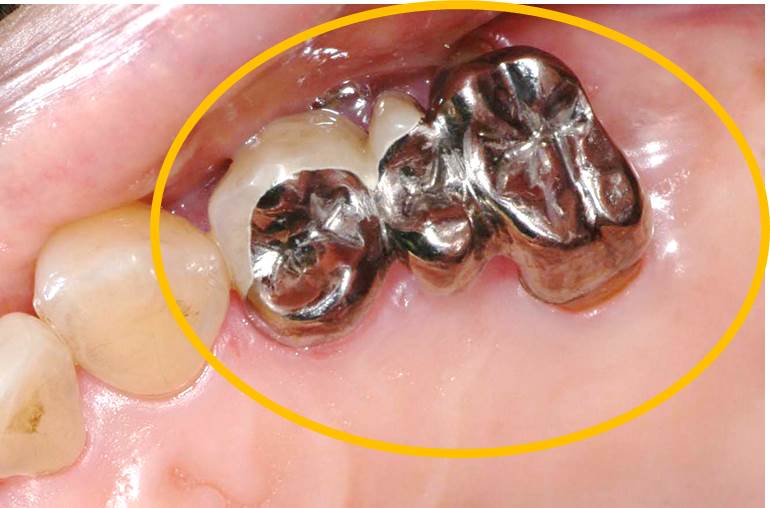

写真は歯周病治療後に補綴装置(ブリッジ)を装着しています。

このブリッジ、歯間ブラシが入りやすいように工夫しています。オレンジ部分の形態を平行にすることにより歯間ブラシ(赤矢印から歯間ブラシを挿入)によるプラークコントロールを行いやすくしています。